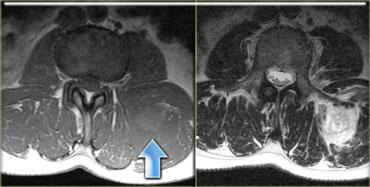

Hình ảnh T1W bên trái của bệnh nhân một tháng sau chấn thương.

Trên hình ảnh sau tiêm Gadolinium, có thể thấy hoại tử ở khoang trước và khoang ngoài.

Khoang sau bình thường.